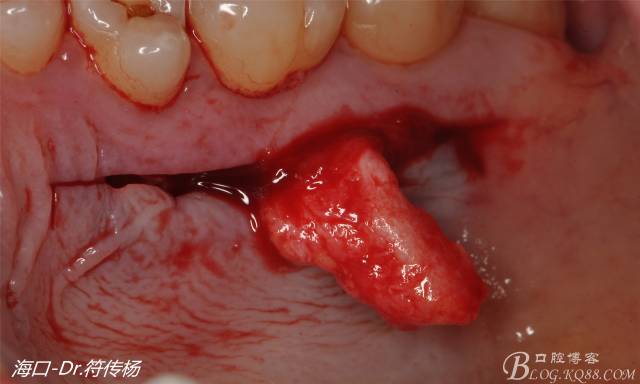

接著從腭部上皮下取出結(jié)締組織

確定取出結(jié)締組織長度是否適當(dāng)